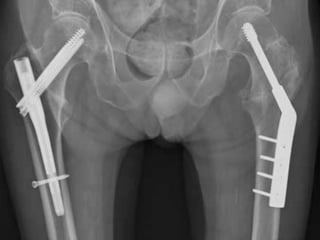

SLIDING HIP COMPRESSION SCREW

Indications

• stable intertrochanteric fractures

Outcomes

• equal outcomes when compared to

intramedullary hip screws for stable

fracture patterns

• The sliding hip screw is the most widely used implant for stabilization

of both stable and unstable intertrochanteric fractures.

• Sliding hip screw side plate angles are available in 5 degree

increments from 130 to 150 degrees.

• The 135 degree plate is most commonly utilized; this angle is easier

to insert in the desired central position of the femoral head and neck

than higher angle devices and creates less of stress

INTRAMEDULLARY HIP SCREW

Also known as the Proximal Femoral Nail (PFN).

• stable fracture patterns

• unstable fracture patterns

• reverse obliquity fractures (56% failure when treated with sliding

hip screw)

• subtrochanteric extension

• lack of integrity of femoral wall

Outcome

• equivalent to sliding hip screw for stable fracture patterns

• use has significantly increased in last decade

SLIDING HIP COMPRESSIONSCREW Indications • stable intertrochanteric fractures Outcomes • equal outcomes when compared to intramedullary hip screws for stable fracture patterns

• The slidinghip screw is the most widely used implant for stabilization of both stable and unstable intertrochanteric fractures. • Sliding hip screw side plate angles are available in 5 degree increments from 130 to 150 degrees. • The 135 degree plate is most commonly utilized; this angle is easier to insert in the desired central position of the femoral head and neck than higher angle devices and creates less of stress

INTRAMEDULLARY HIP SCREW Also known as the Proximal Femoral Nail (PFN). Indications • stable fracture patterns • unstable fracture patterns • reverse obliquity fractures (56% failure when treated with sliding hip screw) • subtrochanteric extension • lack of integrity of femoral wall Outcome • equivalent to sliding hip screw for stable fracture patterns • use has significantly increased in last decade